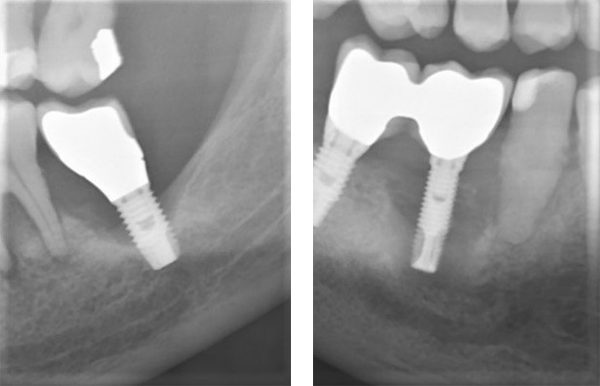

インプラントの寿命はどれくらい?―長期の予知性について正しく知る

インプラントの寿命は、「何年もつか」という単純な年数では語れません。歯科医療では長期の予知性という考え方が重要です。

ストローマン社の情報では、適切な条件下で治療されたインプラントは、10年・20年単位で高い生存率が報告されているとされています。

素材や表面性状の違いが、骨との結合(オッセオインテグレーション)に影響します。